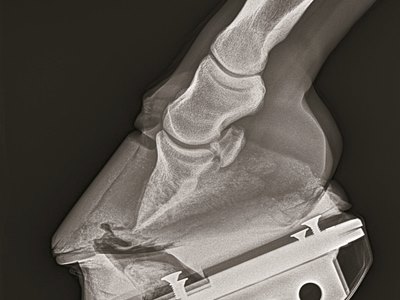

There are three types of laminitis, and all impair the structure and function of the horse's foot. This research provided a snapshot of the active pathways and functions of the hoof, with a focus on supporting limb laminitis—the laminitis to which 2006 Kentucky Derby Presented by Yum! Brands (G1) winner Barbaro succumbed.

The first related to keratin, an important structural protein that helps maintain the structural integrity of materials like hair, nails, and horse hooves. This study was one of the first to examine the changes in the keratin family as laminitis progresses. Some of the keratin-related genes and regulation of the cell's manufacturing process started to diminish as the disease began. Researchers compared this change to when a car gets a flat tire; it may still be running but it loses appropriate function and slows down.

Another type of cell machinery often studied in laminitis are a class of enzymes called metalloproteinases, which are enzymes that help maintain the cytoskeleton. These enzymes must maintain a careful balance. Hooves must be able to grow and not break down under the weight of the horse, which requires a balance of remodeling and building tissues within the hoof. When the metalloproteinases become too active, the hoof begins to lose structural strength. One previous theory for treatment was to stop these enzymes from becoming too active. Targeting these enzymes, however, might also stop hoof growth and likely lead to further issues.